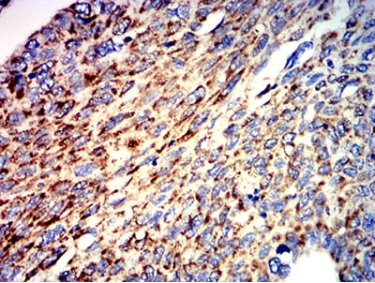

| AC1212 | ATPIF1 Mouse Monoclonal antibody[1F3B8] | 100ug | $367 | 10days |

| AC1212 | ATPIF1 Mouse Monoclonal antibody[1F3B8] | 200ug | $660.6 | 10days |